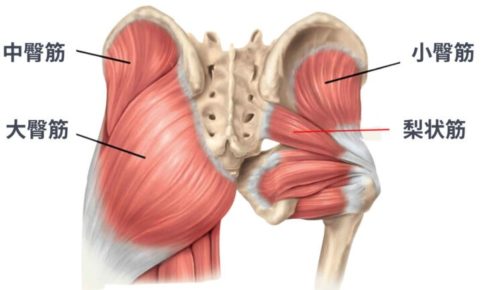

おしりの筋肉は、主に大臀筋・中臀筋・小臀筋という3つの筋肉で構成されています。

「全部まとめておしりの筋肉でしょ?」と思われがちですが、それぞれに役割の違いがあると言われています。骨盤や太ももの骨とつながり、体を安定させたり動かしたりする“土台”として働いているのが特徴です。

2. 大臀筋・中臀筋・小臀筋の位置と役割

まず大臀筋は、おしりの表面にある最も大きな筋肉です。立ち上がるときや階段を上る動作など、力を必要とする場面で使われる“パワー重視”の筋肉とされています。

次に中臀筋は、歩いているときに骨盤が左右に傾きすぎないよう支える役割があると言われています。

さらに小臀筋は、深い位置で股関節を細かく安定させるサポート役として働くと考えられています。

3つの筋肉がチームのように連携している、と捉えるとわかりやすいかもしれません。

3. 骨格との関係から見る筋肉の基礎知識

これらのおしりの筋肉は、骨盤と太ももの骨に付着しています。そのため、おしりの筋肉がうまく使われにくい状態になると、腰や股関節に負担がつながりやすいと言われています。